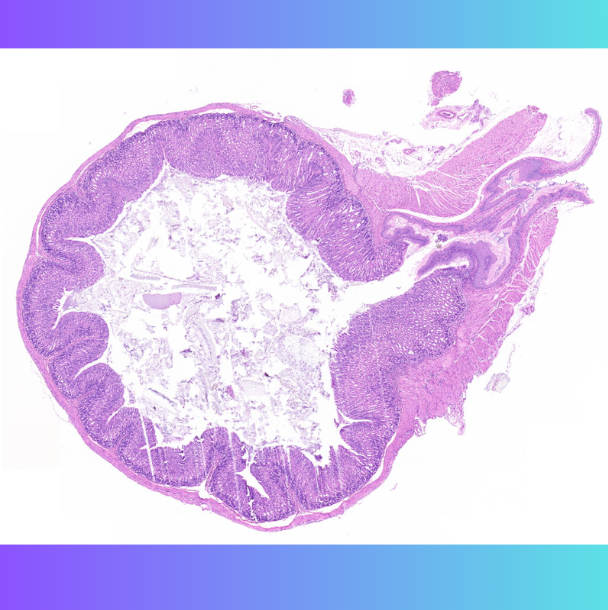

炎性细胞很多,炎症很重的时候,我们就要去找的胃小凹里面有没有幽门螺旋杆菌的感染。显微镜下是可以看到幽门螺旋杆菌的。

然后幽门感染就是会出现腺体里面就很脏,然后这就是因为幽门螺旋杆菌的感染。

小鼠胃组织分离培养的细菌与接种细菌形态及特性相同. 胃窦隐窝可观察到细菌定植 胃黏膜下层可见炎症细胞浸润. 胃组织 DNA 中成功扩增出 H pylori 16SrRNA及cagA基因的目的片段 基因测序结果显示与接种菌株序列完全一致。